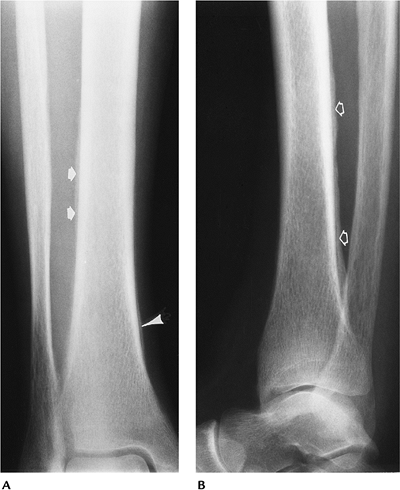

FIGURE 15-32 Secondary hypertrophic osteoarthropathy. AP (A) and lateral (B) radiographs in a patient with chronic pulmonary disease showing periosteal new bone along the lateral tibia (arrows), posterior tibia (open arrows), and medial tibia (arrowhead).